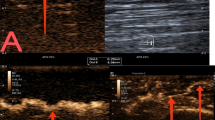

Starfield Sign: Uneven low enhancement with scattered residual enhancement spots (Fig. 3).

A 71-year-old female patient histologically confirmed with follicular lymphoma. (A) Ultrasound image shows a suspicious 37 mm × 12 mm cervical lymph node (arrow), elliptical in shape with uniform cortical thickening. The hilum and hilar blood flow signal are visible, resembling a benign lymph node. (B) Contrast-enhanced ultrasound (CEUS) in the early enhancement phase shows uniform high enhancement. (C) In the late enhancement phase, rapid regression occurs, with uneven enhancement. (D) In the postvascular phase, the lymph node exhibits large perfusion defects, with residual enhancement showing a scattered, spotty distribution. This enhancement pattern is defined as the “starfield sign”—marked by heterogeneous hypoenhancement with multiple discrete, punctate enhancing foci throughout the node in the postvascular phase (10–30 min). This pattern reflects disrupted macrophage distribution and suggests malignancy. Panels a, b, c, and d correspond to schematic diagrams: (a) two-dimensional image, (b) early enhancement, (c) late enhancement, (d) postvascular phase.

Overall performance of CEUS: Of the 23 LNs diagnosed as lymphoma by CEUS, 21 cases (91.30%) were confirmed by pathology, while 2 cases (8.70%) were ultimately diagnosed as benign LNs. Multivariate analysis showed that postvascular phase starfield sign in CEUS is a specific feature of lymphoma (Fig. 3). When the maximum lesion diameter is greater than 3 cm, the sensitivity of starfield sign in the postvascular phase can reach 100% (Table 4). The sensitivity, specificity, accuracy, positive predictive value, and negative predictive value of CEUS for cervical lymphoma were 87.50% (21 of 24 LNs; 95% CI 66.54%, 96.71%), 91.30% (21 of 23 LNs; 95% CI 70.49%, 98.48%), 89.36% (42 of 47 LNs; 95% CI 80.54%, 98.18%), 91.30% (21 of 23 LNs; 95% CI 70.49%, 98.48%), and 87.50% (21 of 24 LNs; 95% CI 66.54%, 96.71%), respectively. The diagnostic performance of US and LCEUS is shown in Table 5.

Normal LNs contain macrophages in both the cortex and medulla20,21. When foreign substances (such as perfluorobutane) enter the LNs through the bloodstream28,29, they can be phagocytosed by macrophages. Therefore, benign LNs exhibit uniform enhancement during the postvascular phase30, which we describe as the “sunburst sign”(Fig. 2). The sunburst sign is an independent indicator associated with benign LNs. Its AUC is 0.81, with a sensitivity of 70.83%, specificity of 91.30%, positive predictive value of 89.47%, and negative predictive value of 75.00%. Therefore, LNs exhibiting the sunburst sign in the postvascular phase are likely benign and may be exempt from biopsy. In contrast, lymphoma cells can invade and destroy the normal structure of LNs, leading to a significant reduction in macrophages and less phagocytosis of microbubbles. Therefore, in the postvascular phase, lymphomas show scattered punctate heterogeneous hypoechoic enhancement within the LNs, which we describe as the “starfield sign”(Fig. 3). Its sensitivity is 91.30%, specificity is 83.33%, positive predictive value is 84.00%, negative predictive value is 90.91%, AUC is 0.87, and diagnostic accuracy is 89% (23 of 21 LNs). There was no difference in the AUC between the combination of CEUS and postvascular phase and US features (P > 0.05). We observed that in lesions larger than 3 cm (21 out of 23 cases), uneven enhancement in the postvascular phase had a sensitivity of 100% for lymphoma, indicating strong diagnostic performance. Based on these results, we believe that CEUS using perfluorobutane as a contrast agent is a promising tool for differentiating suspected cervical lymphomas.